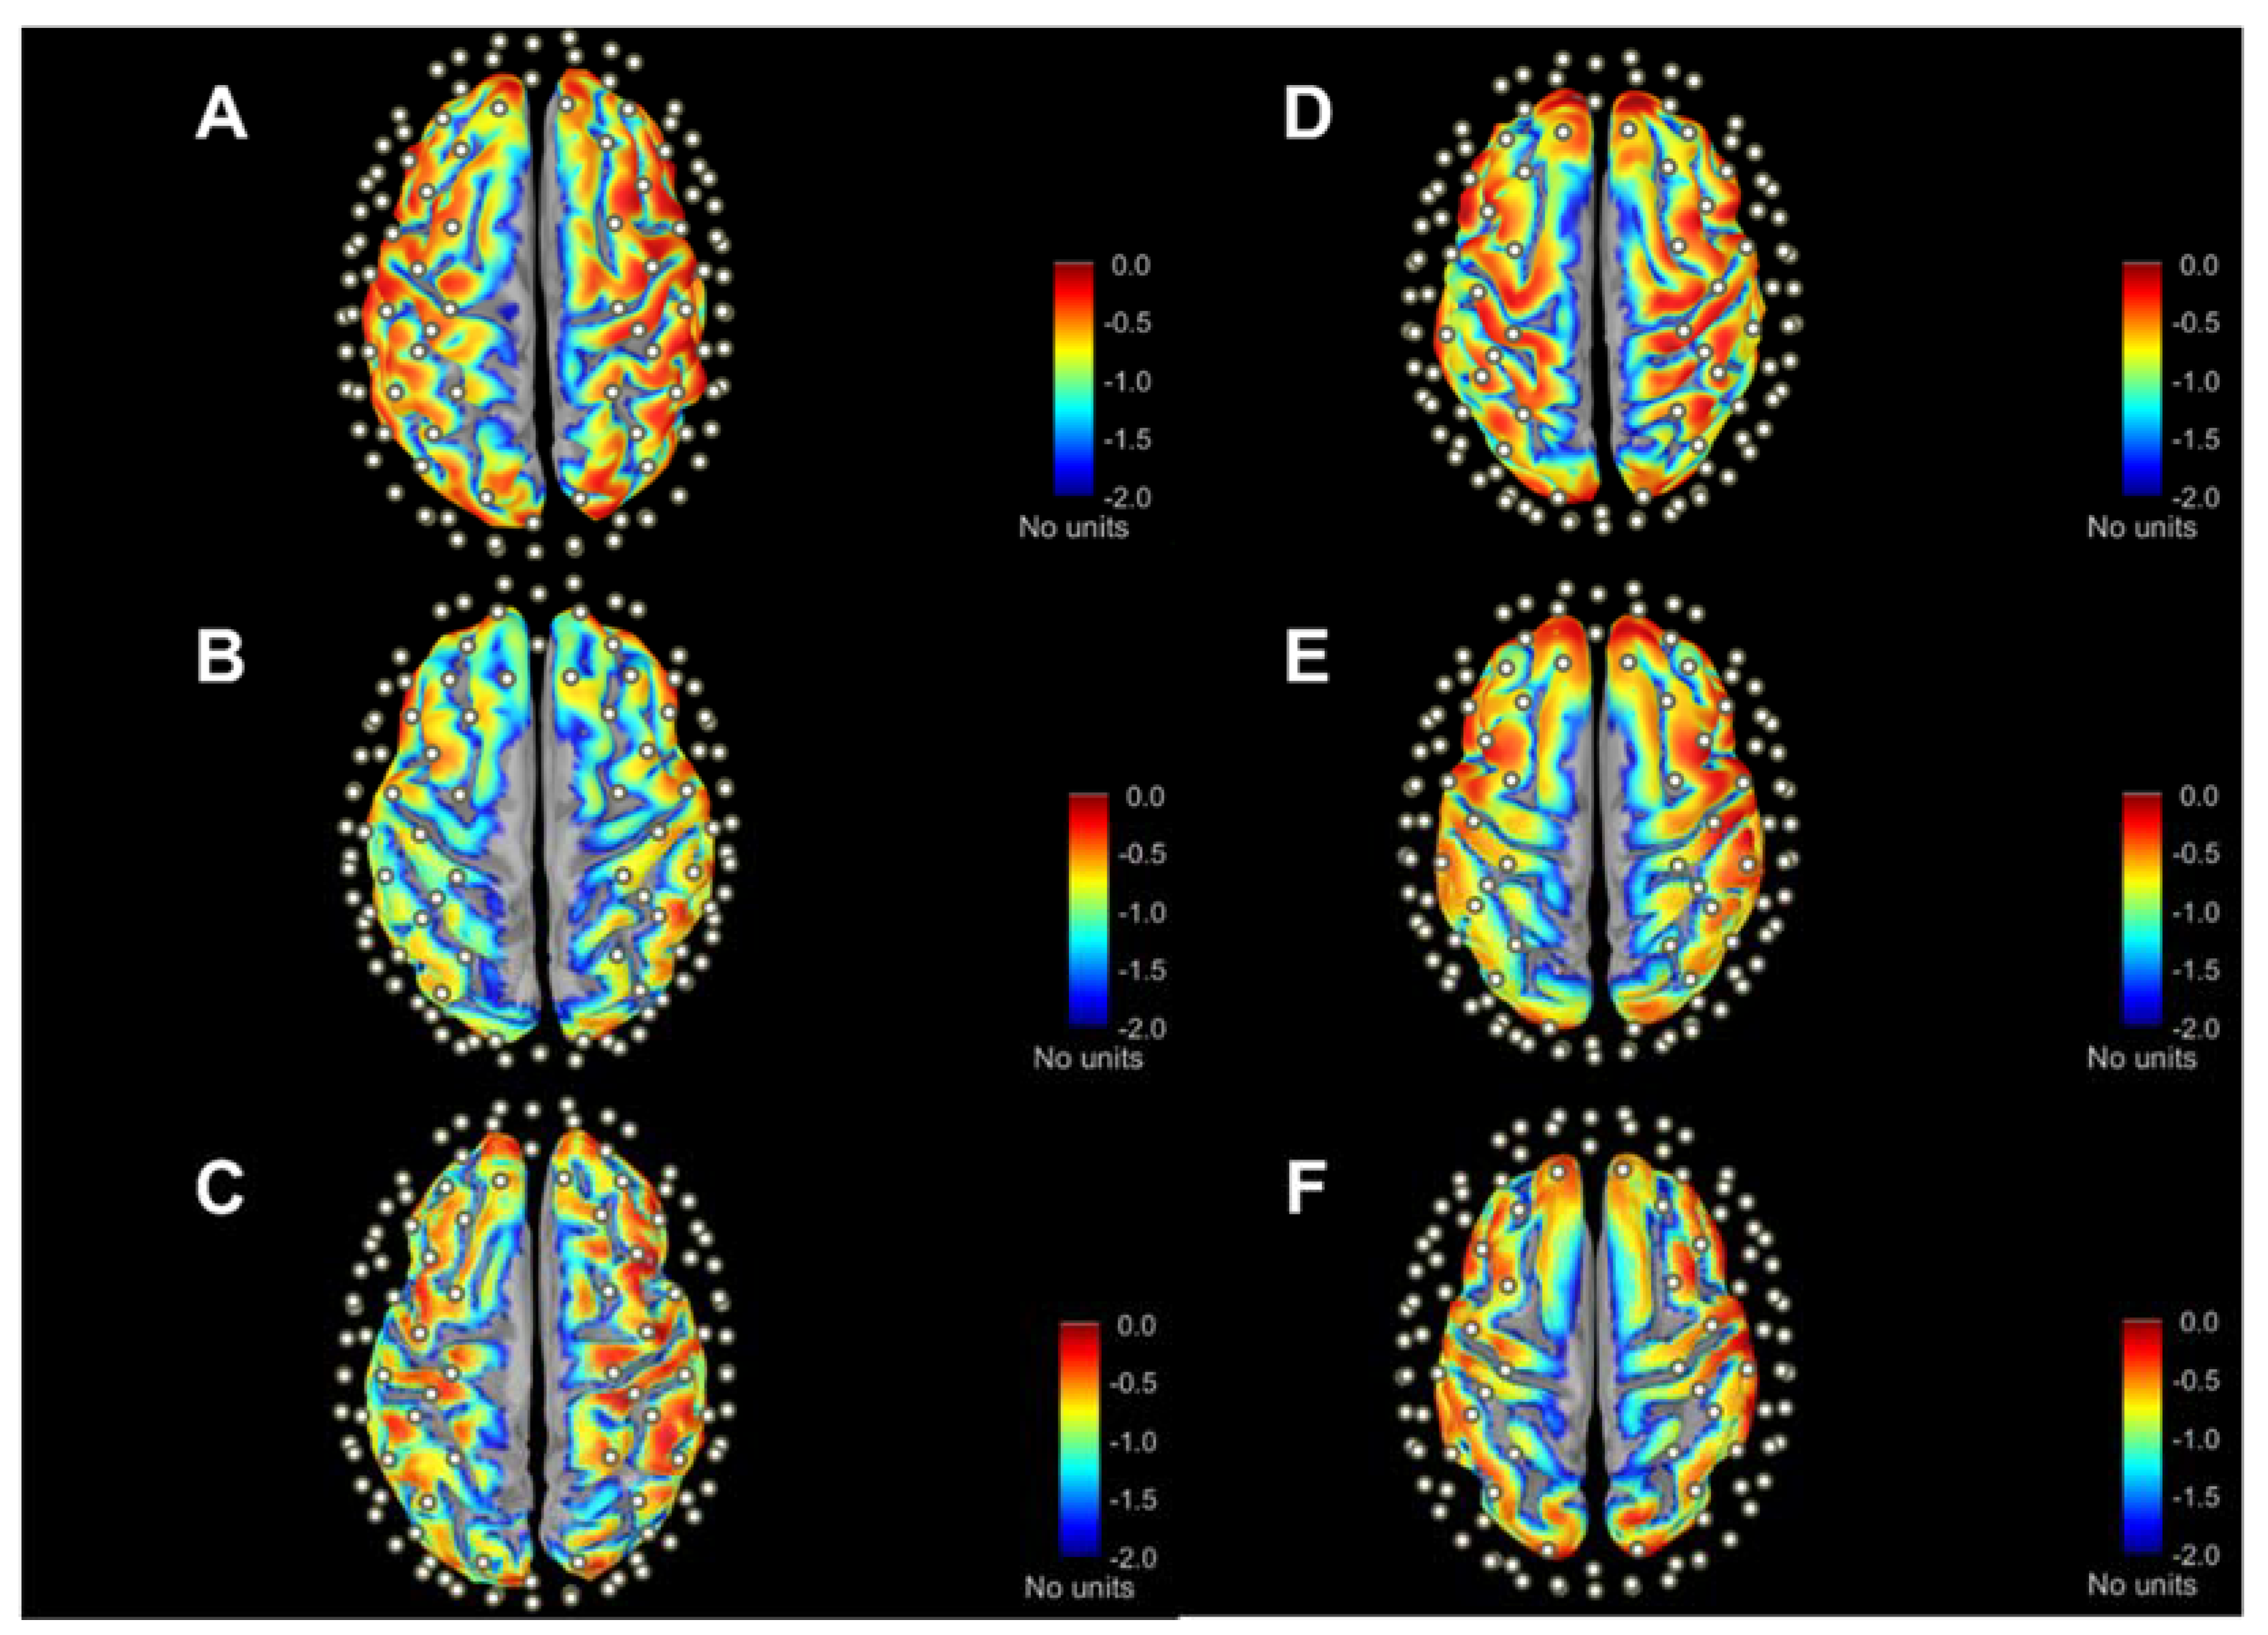

Figure 3 provides an example of sensitivity profile of channel S9D7 (i.e., the representation of A i , j i = S 9 D 7 at source 9 and detector 7), while the red dot represents the S9D7 midpoint as channel position. Considering the log10 scale down to 1/100 (i.e., blue in the color scale), it is evident that the sensitivity profile drops in a short range of depth from the top of gyri to the bottom of sulci. Moreover, there is a noticeable change in the sensed pattern using SSAs (A–C panels) and ABAs (D–F panels), whose variations can be better-quantified with A 2 Ch % indexes (Section 3.3).

The total sensitivity T S j maps on the cortical surface are shown in Figure 4 for three subjects and the three atlases. Values are normalized to the maximum sensitivity (i.e., red color scale) and in log 10 · scale down to 100-fold less (i.e., blue color scale). The qualitative inspection of these maps anticipates the quantitative results of the following analyses. The most evident feature is that the drop in sensitivity with depth shown above for a single channel (S9D7, as example) is maintained, also summing up all channel sensitivities. This confirms that the signal recorded on the scalp surface is almost entirely determined by the gyri. Secondly, along the sagittal plane, the inflation shows a part of the mesial cortex, which is a gray color scale since it is below the considered sensitivity range, hence negligible. Finally, similarities and differences among SSAs (A–C panels) and among atlases (D–panels) are highlighted. Overall, the maps presented in Figure 3 and Figure 4 attain to MC simulation at λ = 760 nm; however, λ = 850 nm provided similar qualitative information.

Figure 3. Graphical representation of channel-wise sensitivity profile placed over motor areas (i.e., S9D7) across three SSAs (AC) and ABAs ((D)—Colin27, (E)—ICBM152, (F)—FSAverage). The respective cortical parcellations of precentral (dark blue) and postcentral (light blue) gyri are also indicated. Sensitivity values are expressed as log 10 · adimensional units. Cortical surfaces were inflated at 40% for visualization purposes.

Figure 4. Maps of total sensitivity in three SSAs (AC) and ABAs ((D)—Colin27, (E)—ICBM152, (F)—FSAverage) according to anteroposterior direction. Sensitivity values are expressed in log 10 · scale. Cortical surfaces are inflated at 40%. All maps refer to λ = 760 nm, while maps for λ = 850 nm are not shown since they display similar patterns.